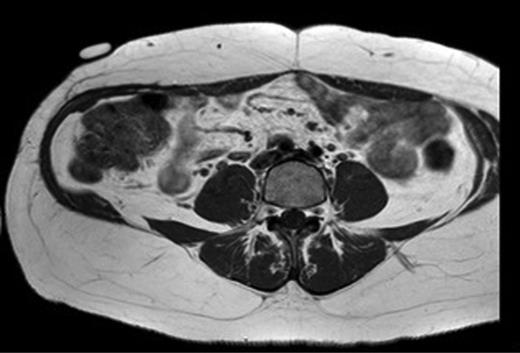

A 43-year-old Caucasian female presented to her General Practitioner in April 2012 with a 2-year history of a firm, painful swelling in the right flank. MRI revealed a 5.0 × 6.0 × 7.0 cm enhancing lesion with areas of necrosis, which was invading the antero-lateral abdominal wall (Fig. 1 ). With radiological features highly suggestive of a sarcoma, she underwent an ultrasound-guided biopsy, which classified the mass as a borderline myoepithelial tumour. The patient underwent an uncomplicated resection of the mass, which left a 10 × 10 cm right-sided antero-lateral abdominal wall defect. The defect was repaired using a Biodesign® biological graft. Initially, a layer of the biological mesh was used to cover the intact peritoneum with attachments cranially to the ribs and inferiorly to the right iliac crest. The external oblique was mobilized to partially cover the mesh, and a further layer of the biological mesh attached over it with Ethilon™ (Fig. 2). The patient had an uncomplicated postoperative recovery. The tumour histology revealed a 6.5 × 6.0 × 5.5 cm myxoid mass; immunohistochemistry analysis favoured a benign/borderline myofibroblastic tumour. At 24-month follow-up, she had good wound healing with a small area of paraesthesia inferior to the scar. An MRI showed good graft incorporation and no evidence of disease recurrence or hernia (Fig. 3).

T1 MRI showing a soft tissue abdominal wall tumour involving external oblique, internal oblique and transversus abdominis and not involving the peritoneum (arrow).